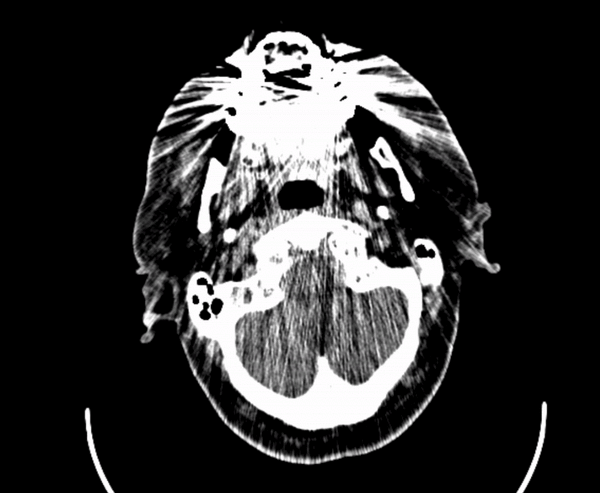

If a picture is worth 1000 words, how many words is a DICOM?

A tool for interactive case presentations